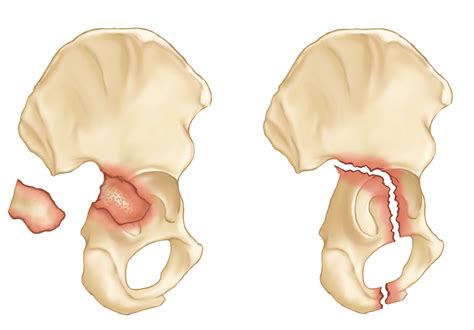

Classification of Fractures of the Acetabulum

Fractures of the acetabulum are classified based on the pattern and location of the fracture. The most commonly used classification system is the Letournel and Judet classification, which categorizes acetabular fractures into ten distinct types:

Type Description

Posterior Wall Fracture of the posterior wall of the acetabulum

Posterior Column Fracture of the posterior column of the acetabulum

Anterior Wall Fracture of the anterior wall of the acetabulum

Anterior Column Fracture of the anterior column of the acetabulum

Transverse Horizontal fracture line across the acetabulum

T-shaped Transverse fracture with a vertical component

Posterior Column and Posterior Wall Combined fracture of the posterior column and wall

Anterior Column and Posterior Hemi-Transverse Combined fracture of the anterior column and posterior hemi-transverse

Both Columns Fracture involving both the anterior and posterior columns